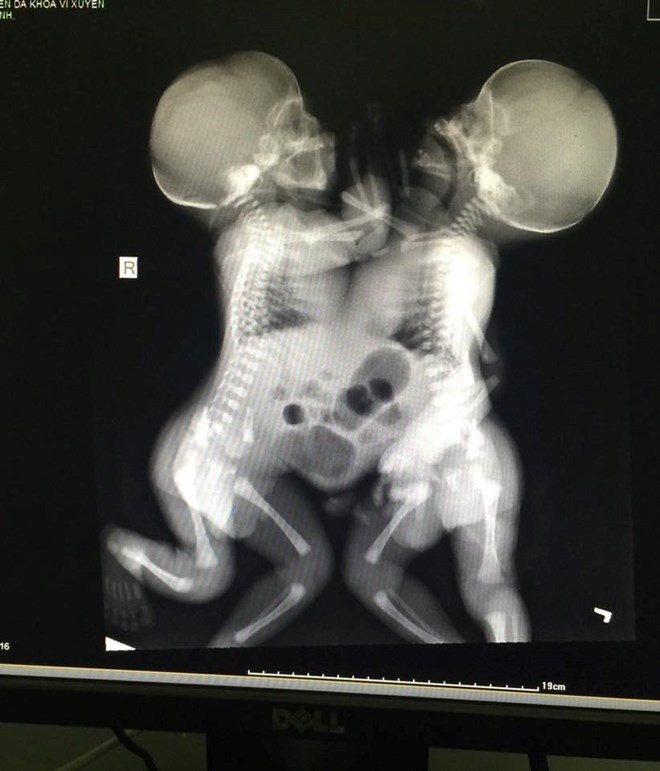

Lúc ấy các bác sĩ chỉ biết là thai đôi chứ không biết là hai thai dính nhau. Trong quá trình mổ sinh, bác sĩ phát hiện 2 bé trai dính liền với nhau từ ngực đến bụng, chung dây rốn, 2 thai có trọng lượng 4.900 gr.

| Cặp sinh đôi dính nhau. |

Sau mổ 2 cháu đang được chăm sóc tại khoa Nhi - Bệnh viện Vị Xuyên. Sáng ngày 14/7, bệnh viện đã hội chẩn có cả ban lãnh đạo bệnh viện và qua thăm khám sơ bộ, các bộ phận tim phổi thận của hai cháu vẫn tách rời nhưng để chẩn đoán tốt hơn bệnh viện phải chuyển hai bé xuống Hà Nội.